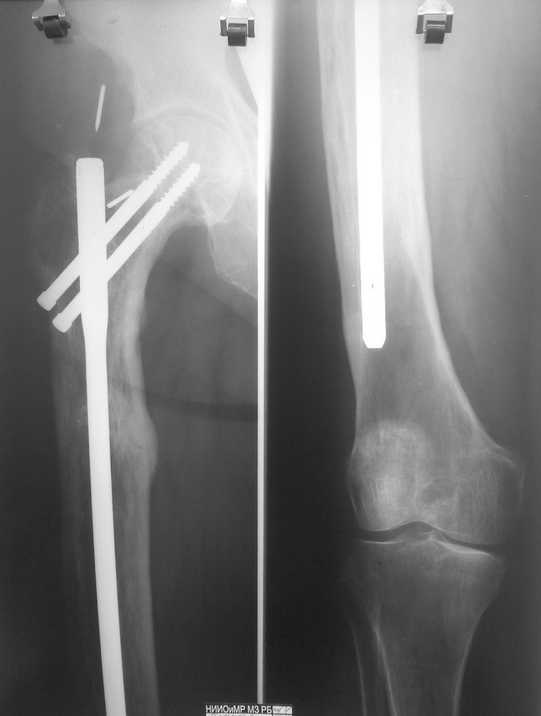

Год назад посылал сообщение о патологическом переломе

Год назад посылал сообщение о патологическом переломе на фоне болезни

Педжета (http://www.weborto.net/forum/1197022316/). Вот, в итоге, все

зажило. Сообщение посылаю так, для ознакомления, может кому-то будет

интересно. Всех с Рождеством!